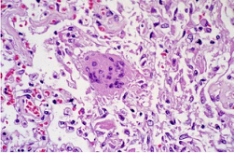

- 2023-10-19由于各種細胞成分的化學性質(zhì)不同,經(jīng)改良的巴氏染液染色后呈現(xiàn)各種不同顏色,如胞質(zhì)中的主要成分是蛋白質(zhì),一般呈堿性,可與帶負電荷的酸性染料結合染成紅色、綠色或桔黃色,而細胞核的主要成分為DNA,可與帶正電荷的堿性染料結合染成紫藍色。巴氏染色液 染色結果:胞核染為藍紫色;鱗狀上皮基底層、中···